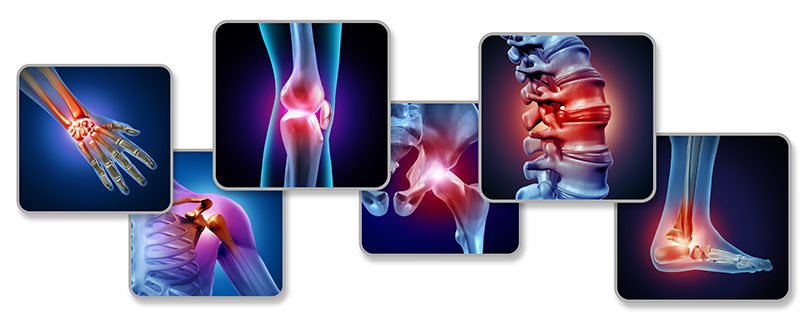

For years, joint pain has been managed rather than truly addressed, leaving millions dependent on pills, injections, or surgery. Recently, researchers have begun discussing a little-known method that focuses on restoring the body’s natural ability to support joint function. Instead of masking symptoms, this approach targets inflammation, cartilage nutrition, and joint lubrication at the source. Early observations suggest it may help improve mobility and comfort without aggressive medical interventions. As interest grows, many are calling this method a promising shift toward more natural and sustainable joint care.